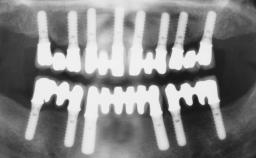

Immediate Loading of Six Implants in the Maxilla and Final Restoration with a Full-Arch Gold/Ceramic FDP Involving the Concept of Tilted Implants

# of Implants 6

Type of Implants One-Piece|Reduced-Diameter

Prosthesis Type FDP